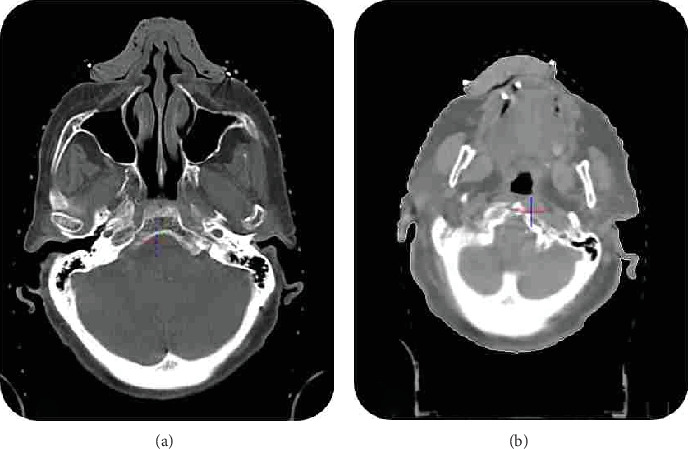

Introduction: Skin cancer is the most prevalent cancer in Iran. While surgical excision is the primary treatment, radiation therapy (RT) plays a crucial role, especially for tumors in critical anatomical locations. This case report evaluates the performance of handmade boluses for skin cancer RT using 6 MV photons. Case Presentation: Two patients with lip squamous cell carcinoma (SCC) and nasal basal cell carcinoma (BCC) were treated using 6 MV photon RT with handmade boluses. Dosimetric evaluation using EBT2 Gafchromic film was performed to verify the delivered radiation doses. For the lip SCC patient, the measured dose was 3.9% higher than the planned 73.85 Gy. For the nasal BCC patient, the measured dose was 3.48% higher than the planned 75.60 Gy, demonstrating the high accuracy of the handmade bolus approach. Discussion: The use of patient-specific, handmade boluses demonstrated several advantages, including reduced air gaps and improved dose delivery accuracy compared to commercial boluses. The consistent bolus positioning minimized interfraction setup variations, leading to lower standard deviations in the measured doses. While this study did not directly quantify the air gap, prior research has reported air gap reductions of over 72% with patient-specific boluses. Conclusion: This case report supports the effectiveness of handmade boluses in combination with 6 MV photons for skin cancer RT, particularly in resource-constrained settings where advanced treatment modalities may not be readily available. The handmade bolus approach provides an accessible solution to enhance the precision of skin cancer RT.